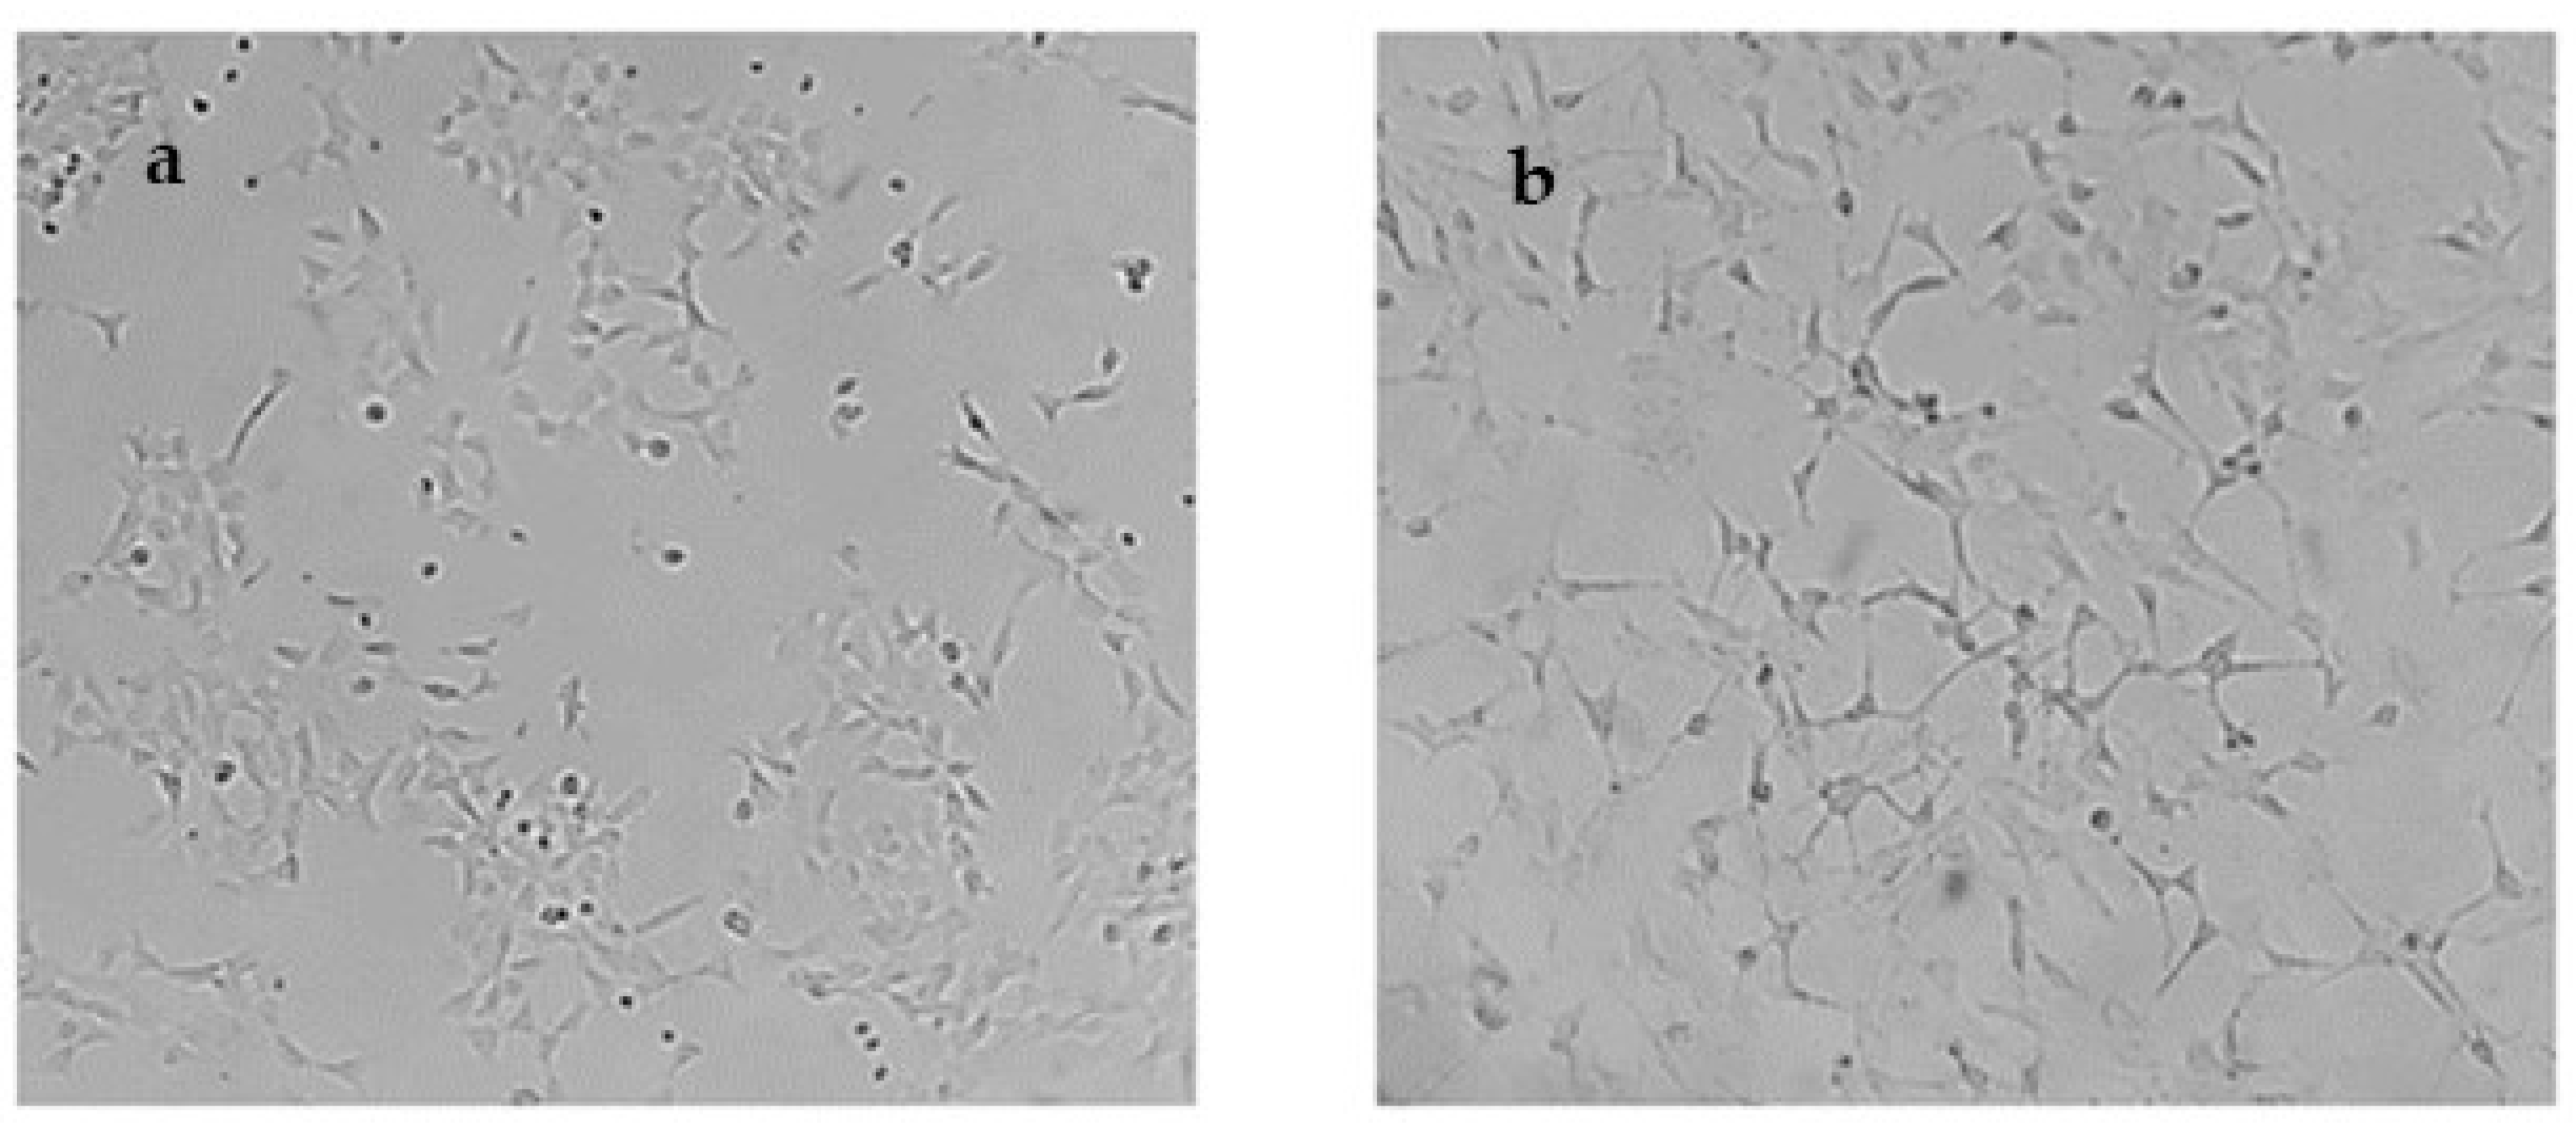

2.5. In Cellulo Assessment of the Compounds in SH-SY5Y Cells

4.5. Cell Line and Differentiation